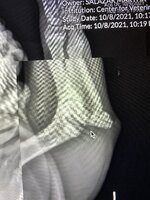

Hello everyone! I’m a 4 month old EB with a broken growth plate šŸ˜¢ā€¦ā€¦ I live in Texas, my mommy started a go fund me for my surgery and is in desperate need of help… We are wondering if everyone could share or even help us with our go fund me… I understand there’s a lot of scammers out there so my mommy post daily on my Instagram with updates copy’s of bills and more to ease everyone’s minds. A share goes a long way and any lil bit will help me get closer to my surgery.

• 5DEDA12F-9E3F-447B-827C-A278D05C95F6.jpeg

5DEDA12F-9E3F-447B-827C-A278D05C95F6.jpeg

216.1 KB · Views: 153